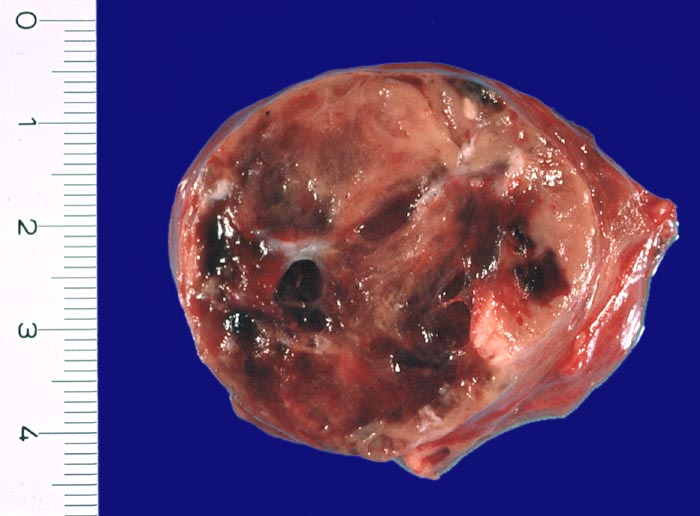

- Anschnitt eines grossen mikrofollikulären Knotens (autonomes Adenom) mit angedeuteter Kapsel und zentraler Einblutung. Oben zwei weitere kleine Satellitenknoten.